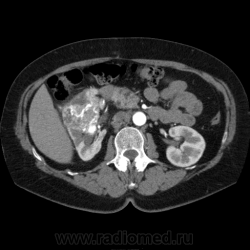

Солитарное кистовидное образование правой почки с неравномерно утолщенными стенками, у узлами в капсуле, накапливающими контраст. Фасция Гарота справа тяжистая. По классификации - киста 4-й категории, крайне велика возможность малигнезации. Может, показалось вовлечение парааортальных лимфоузлов?

В 1986 г. M.A. Bosniak создал “рабочую” классификацию кистовидных образований почек, которая позволяет предположить доброкачественность или злокачественность кистозных образований при распределении их по радиологическим критериям на 4 основные категории. Образования I и II категорий являются заведомо доброкачественными и поэтому нуждаются в динамическом наблюдении или, по показаниям, в лечебной пункции со склеротерапией под контролем УЗИ или КТ. Образования III категории могут быть как доброкачественными, так и злокачественными, а образования IV категории – кистозные почечноклеточные раки.

IV категория – поражения явно злокачественные, обычно кистозные почечно-клеточные карциномы. Основными симптомами кистозной опухоли при КТ являются: неправильная форма кисты, негомогенность структуры образования с участками некроза, деформация почки, нечеткая граница между кистой и паренхимой почки, плотностные показатели могут быть выше, чем в кистах (+20…+40 Н), т.е. близкие к плотности почечной паренхимы. Капсула имеет неравномерную толщину, часто обызвествлена по периферии. Возможна визуализация дополнительных фокусов образования (кажущееся увеличение образования в размерах и изменение его конфигурации) после введения контрастного вещества. Но самым важным симптомом является увеличение плотности внутреннего содержимого после внутривенного введения контрастного вещества. Часто на серии срезов удается выявить эндофитные гребневидные фестончатые разрастания, выступающие в просвет кистозной полости. Особенно хорошо этот мягкотканый васкуляризированный компонент опухоли проявляется при внутривенном контрастировании

Всё верно, я тоже пользуюсь данной классификацией по Босняку, кистозно-солидное образование правой почки я отнёс к 4 категории, нужно отметить, что преобладает кистозный компонент, но солидный компонент довольно приличный и значительно накапливает контрастное вещество до 80-90HU, четко капсулу образования не отграничить. Ко всему этому в паренхиматозную фазу четко дифференцируются единичные парааортальные и паракавалльные л/узлы. С большей степенью вероятности в данном случае cr почки. Пациентка на следующей неделе будет госпитализирована для верификации.

Описание изменений, выявленных при микроскопическом исследовании: опухоль представлена крупными альвеолярными структурами из светлых, оптически пустых клеток с мелкими гиперхромными ядрами, опухоль частично инфильтрирует капсулу почки, полностью прорастает стенку почечной лоханки, образуя полиповидные структуры. Одиночные опухолевые эмболы в сосудах почки. Отдельно присланный узел представлен тканью почки с опухолевым узлом, строение которого соответствует выше описанной опухоли. В воротах почки патологических образований не найдено. Во всех исследованных лимфоузлах (6 шт.) метастазы опухоли с замещением всей ткани лимфоузлов.

Патоморфологическое заключение: массивный светлоклеточный почечно-клеточный рак почки с частичной инфильтрацией капсулы, прорастанием в ЧЛС, опухолевыми эмболами в сосудах, множественными метастазами в забрюшинные лимфоузлы (6 шт